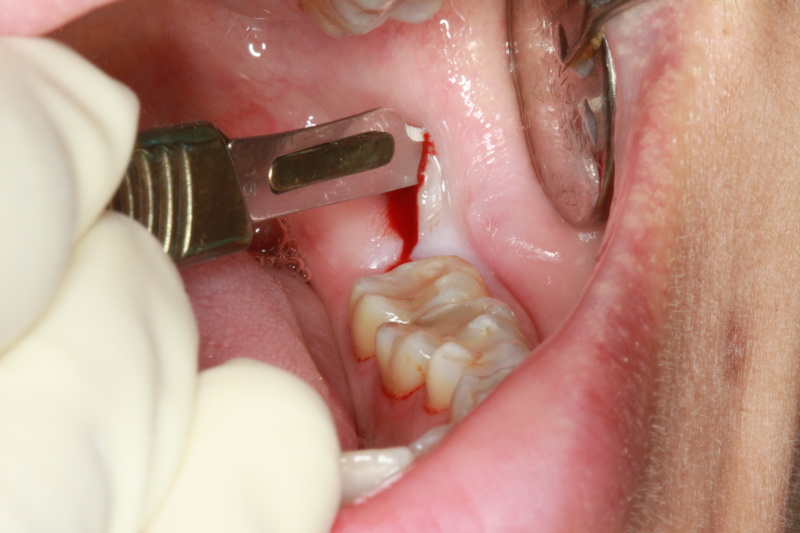

- The procedure can involve an incision (cut) in the gum close to the tooth.

- Sometimes some jaw bone around the tooth is removed with a drill and alsothe procedure can be made easier by sectioning (cutting up) the tooth itself into smaller pieces.

Fig 3 : Incision made to expose the wisdom tooth

Fig 4 : Impacted wisdom tooth exposed